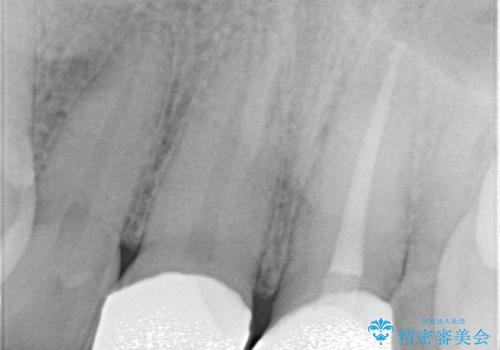

精密根管治療後、オールセラミッククラウンで治療を行いました。

治療後、違和感は無くなりました。

治療後、違和感が無くなり、被せ物で歯の長さが揃い見た目も改善されとてもご満足していただけました。